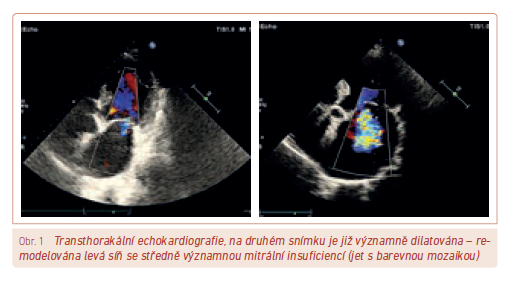

V managmentu léčby fibrilace síní máme dvě možné strategie: za prvé je to snaha o nastolení a udržení sinusového rytmu, za druhé kontrola srdeční frekvence ponechané fibrilace síní. Prakticky všichni pacienti by měli mít antikoagulační léčbu (nejen pacient s CHADsVASc score 0–1). Obvyklou komorbiditou u pacientů s fibrilací síní je arteriální hypertenze, kterou zvládáme kombinační léčbou, často ve fixní podobě. Pokud se rozhodujeme pro elektrickou kardioverzi, neotálíme, než pokročí remodelace levé síně (obr. 1).

Při úvodním nasazení nových antikoagulancií odpadávají kontroly INR, které zbytečně prodlužují čekání na kardioverzi, pokud pacienta warfarinizujeme. Toto čekání můžeme zkrátit vyloučením trombu v oušku levé síně jícnovou echokardiografií (obr. 2).